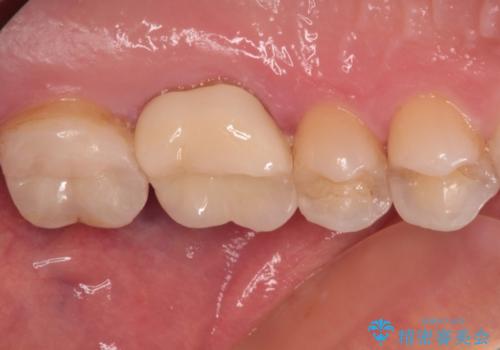

強い咬合力を負担する第一大臼歯であるため、根管治療後は速やかにオールセラミッククラウンにて補綴治療を行うこととしました。

初診時は神経組織の生活反応が認められましたが、2日後に処置を行ったときには、既に反応はなくなっている状態でした。

神経組織は壊死が始まっておりましたが、初回処置後には痛みを感じることもなくなり、2回目に無事に根管治療を終えることができました。